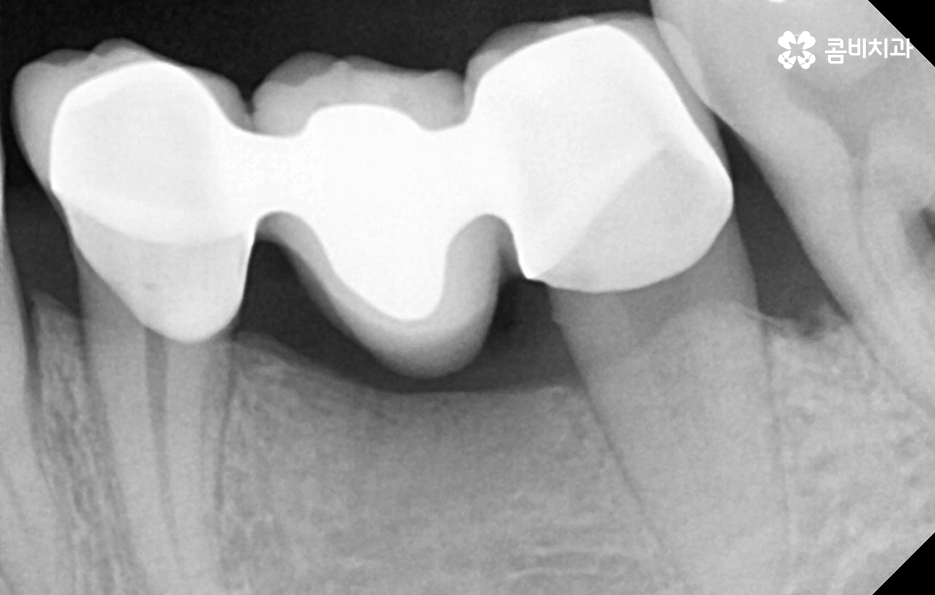

40대임플란트 치료에 대해 알아보신다면 우선 치아를 상실한 원인에 따라서 치료 방법이 다소 차이가 날 수 있는데요. 대표적으로 충치가 심해져서 발치를 하게 된 사례와 치주염으로 인해 잇몸이 약해져서 발치하게 된 사례로 구분해 본다면 충치 만으로 치아를 발치한 경우 잇몸 상태가 양호할 때 원데이임플란트로도 치료가 진행되거나 무난하게는 일반적인 임플란트 치료 과정으로 진행될 수 있어요

물론 앞니가 사고로 부러지거나 어금니에 충치가 생겨서 발치하게 된 사례와 같은 경우에는 비교적 잇몸 상태는 양호한 경우도 많기 때문에 임플란트를 알아보시면 흔히 접하게 되는 원데이임플란트와 같은 치료 방법이 가능한 분들도 있을 거예요